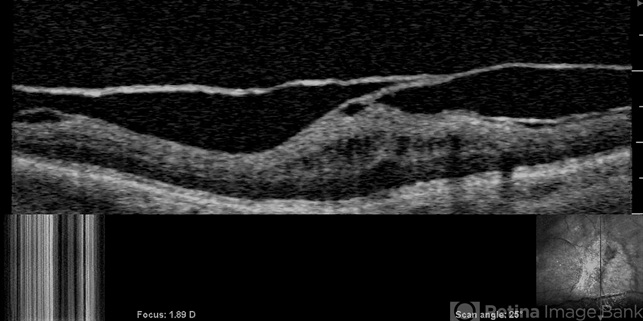

- vitreoschisis

- OCT of the left eye in a patient with macular pucker (see SLO image below to right) demonstrates splitting of the posterior vitreous cortex in two separate places. Tangential traction caused thickening of the underlying macula. [For histopathology see: Gupta P, Yee KMP, Garcia P, Rosen RB, Parikh J, Hageman GS, Sadun AA, Sebag J: Vitreoschisis in macular diseases. Brit J Ophthalmol 2011;95(3):376-80]